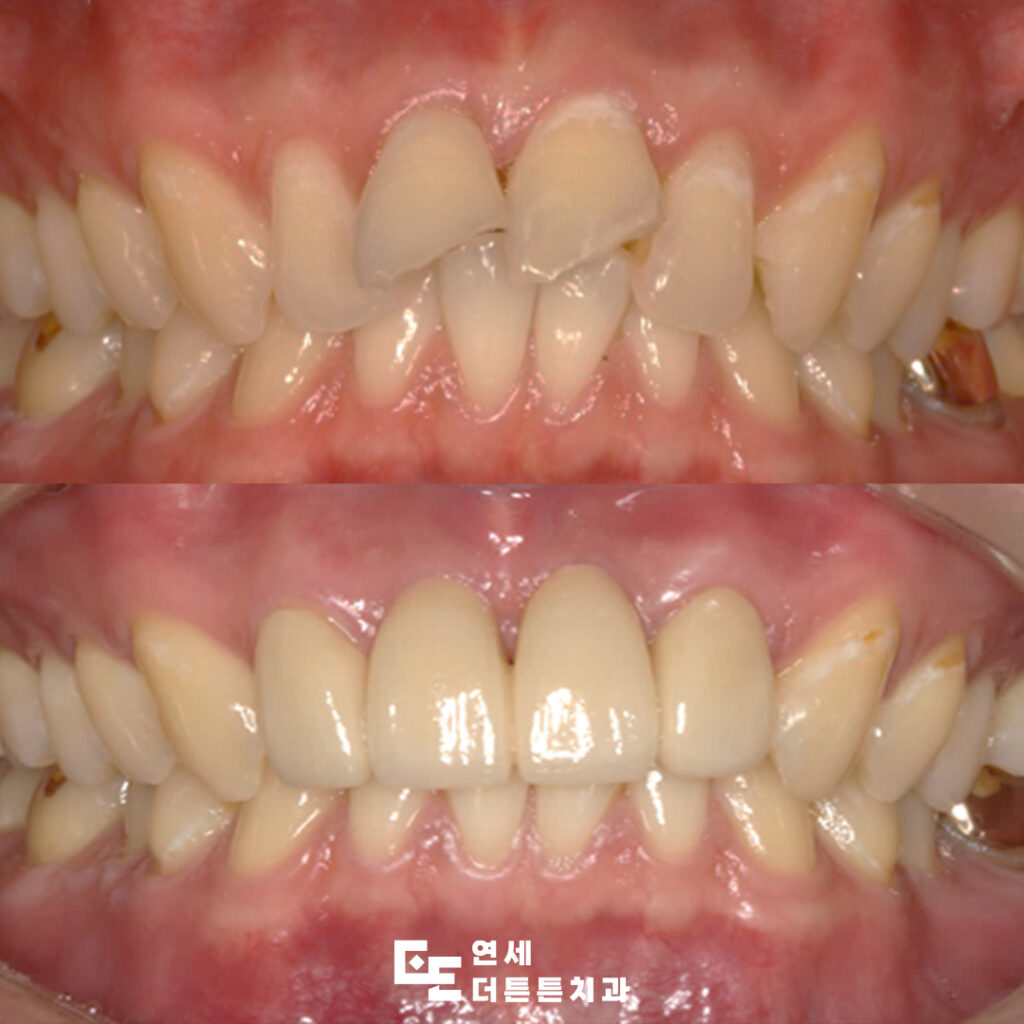

오늘은 외상으로 인해 깨진 앞니를

발치한 후 양쪽 치아를 걸어 브릿지로

수복하신 환자분의 케이스를 소개해 드리려고 합니다.

환자분은 20대 남성분으로

도로에서 넘어지면서 앞니에 외상을 입어

내원해 주셨습니다.

내원 당시 구내 사진과

x-ray 사진을 통해 진단해 본 결과,

가장 오른쪽의 앞니는 뿌리까지 부러져

있음을 확인할 수 있었으므로

발치를 결정할 수밖에 없었는데요.

앞니 두 개 발치 후 임시치아를 사용하면서

충분히 경과를 지켜본 뒤 최종 보철물을

시행하여 마무리하였습니다.

환자분께서는 돌출된 윗입술이

개선된 것 같으시다며,

심미적으로도 예뻐서 매우 만족하셨고

기능적으로도 불편함 없이 아랫니와

올바르게 교합될 수 있도록 조정해 드렸습니다.